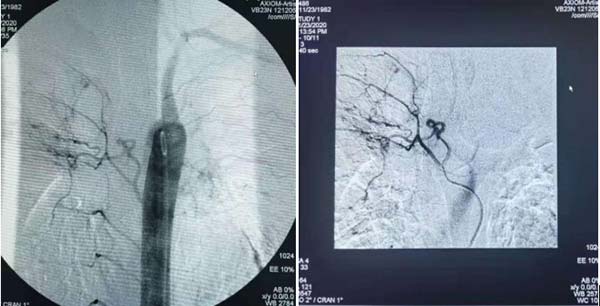

胸主动造影造影提示右支气管动脉支气管动脉迂曲扩展与右侧肋间动脉共干,左肺支气管动脉、左侧胸廓内动脉造影剂外溢。

患者右肺支气管动脉与肋间动脉共干,应用微导管超选后栓塞。

应用C2导管超选左侧支气管动脉后栓塞。